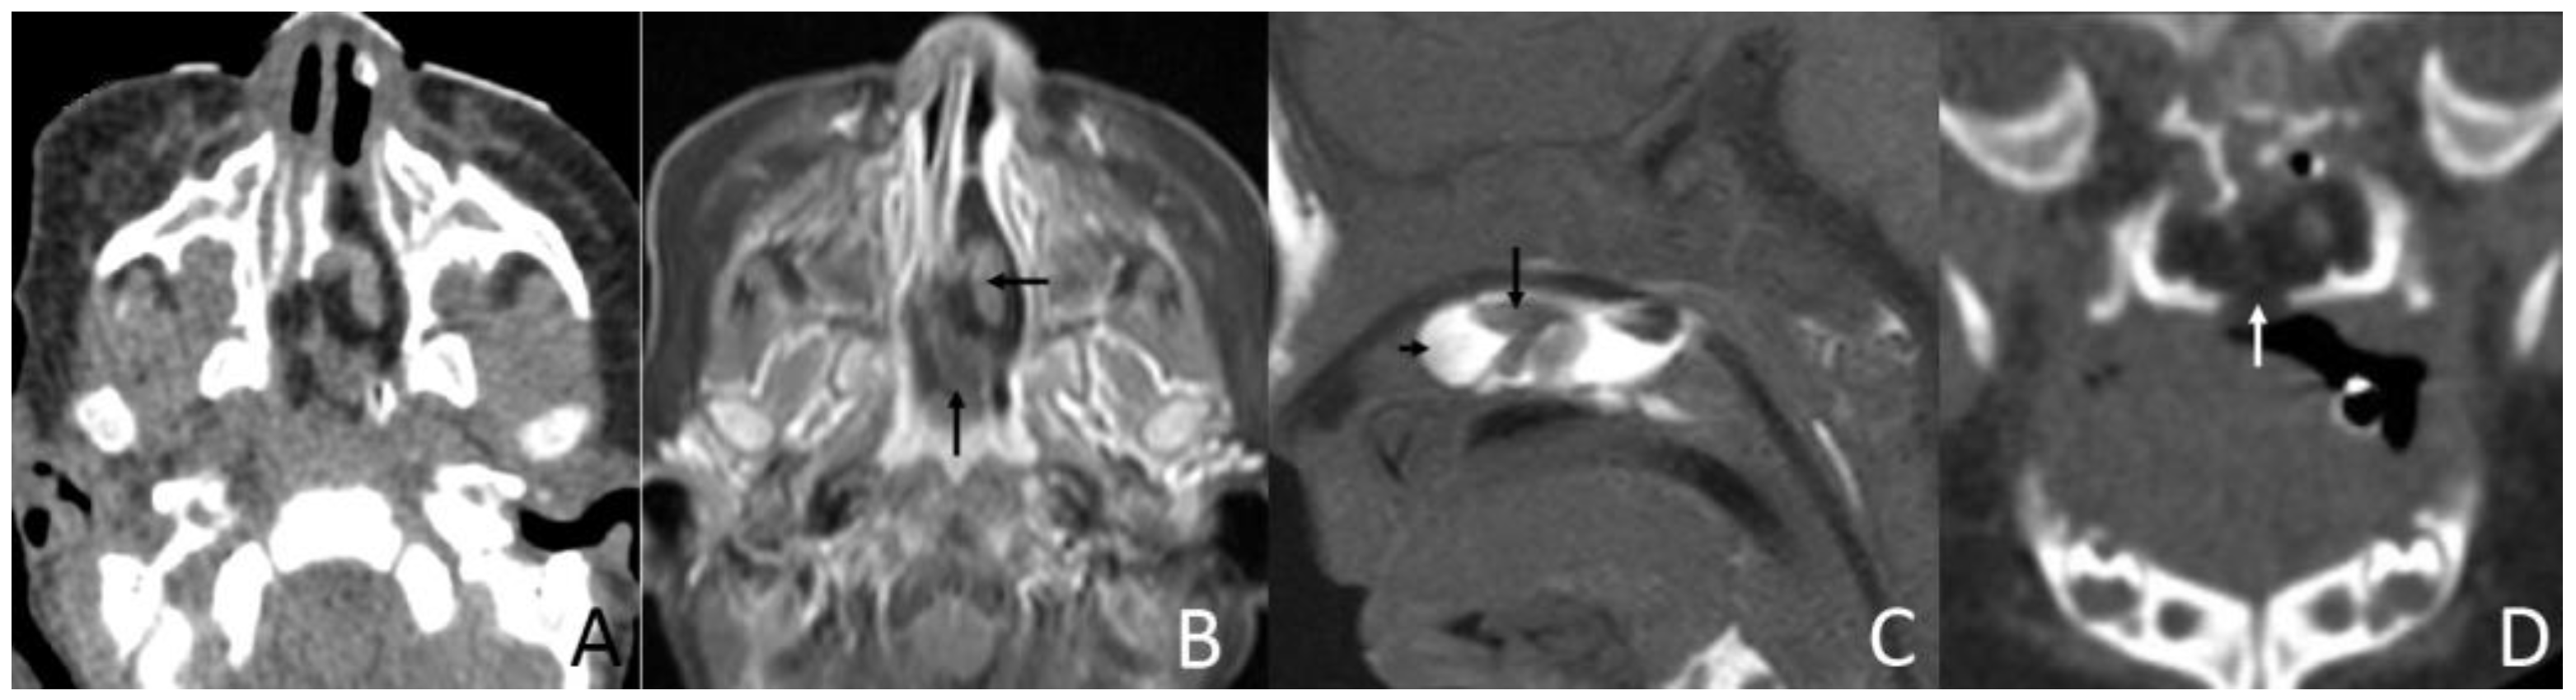

Figure 1. CT and MRI of a 2-month and 17-day girl presenting shortly after birth with dyspnea and inspiratory stridor. (A) Axial CT, displayed in the soft-tissue window, shows the soft palate mass protruding to the left nasal cavity and blocking the bilateral choanae to be of predominantly low attenuation, containing an irregular moderate-attenuation stalk. (B) Axial, postcontrast, T1W-SPIR MRI shows that the lesion’s stalk is slightly enhanced (arrows), but the rest of the lesion is not enhanced. (C) Sagittal T1-weighted MRI shows an irregular mass in the soft palate and left nasal cavity that mainly has a high-signal (short arrow) with an irregular low-signal central stalk (long arrow). (D) Coronal CT, displayed in the bone window, shows the soft palate mass associated with the cleft palate (arrow).

The size of masses varied from 0.6 to 4.3 cm. There were 11 (78.6%) cases with the largest diameter of the mass greater than 2 cm. The shapes of the masses were varied. Eleven (78.6%) cases presented with typical pedicled masses containing fat and a central core of soft tissue, including sausage-like masses in five (35.7%) cases, tongue-like masses in four (28.6%) cases, and pear-like masses in two (14.3%) cases. Of the eight patients who underwent MRI scans, there were five (62.5%) patients whose masses had high signal intensity on T1-weighted and T2-weighted sequences with a low-signal central core whose signal intensities were similar to those of muscles. The high signal intensities on all sequences were similar to the fat signals and attenuated by fat suppression. The central core demonstrated mild enhancement following intravenous gadolinium administration, while the surrounding components of the fat signals demonstrated no enhancement in one case (Figure 1). There was no reduced diffusion of the five patients who underwent DWI. Via CT, there were 10 (83.3%) cases whose masses appeared as well-circumscribed fat attenuation masses surrounding a central core of soft tissue. The central core was mildly enhanced following intravenous iodixanol administration, but the fat components were not enhanced in one case (Figure 2). There were five patients who received both MRI and CT.

3.3. Associated Malformation

Upon MRI, most of the masses were found to have heterogeneous high signal intensity on T1-weighted and T2-weighted sequences with a low-signal central core whose signal intensities were similar to those of muscles. The high signal intensities on all sequences were similar to the fat signals and attenuated by fat suppression. The central core demonstrated mild enhancement following intravenous gadolinium administration, while the surrounding components of the fat signals demonstrated no enhancement. The central core helps us trace the origin of the mass, which is important for the choice of surgical method. Characteristic imaging features on CT include well-circumscribed masses containing fat and linear soft tissue–density components centrally that correspond to the fibrovascular stalk [2]. The central core was mildly enhanced, as expected for fibrous tissue, but the fat components were not [23]. These findings corresponded well with the MRI and CT features previously described [24,25]. Intracranial or intraspinal extension was not found in any of the lesions in the present study, which was consistent with existing reports.